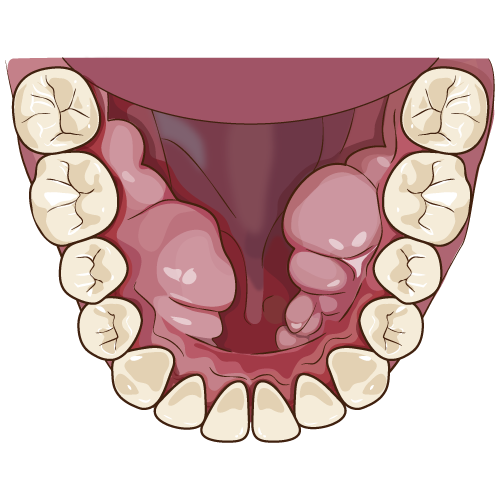

インプラントとは

失われた歯の代わりとなる物。チタンでできていて、入れ歯やブリッジと違い骨に直接結びつくため、自分の歯と同じようにつかうことができます。